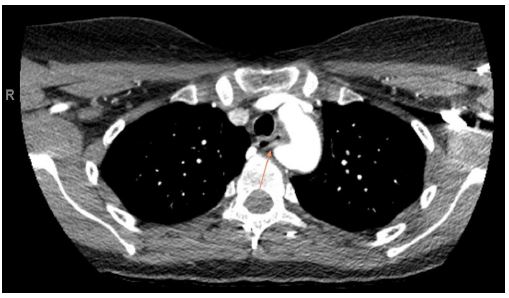

A 39-year-old female with a past medical history of chronic bronchitis presented for evaluation of progressive dysphagia. She reported a long-standing history of difficulty swallowing, often experiencing transient substernal obstruction of solid food and occasionally liquids. Her symptoms subsequently progressed until she was tolerating only minimal oral intake accompanied by unintentional weight loss, prompting her to seek care. A barium esophagram revealed a 2.7 cm extrinsic compression in the upper esophagus. A CT angiogram of the chest identified an aberrant right subclavian artery compressing the esophagus. An Esophagogastroduodenoscopy (EGD) confirmed extrinsic compression in the upper third of the esophagus, consistent with suspected dysphagia lusoria. Esophageal biopsy showed normal mucosa. She underwent right subclavian to carotid transposition and Thoracic Aneurysm Endovascular Repair (TAVER). At a follow-up assessment two weeks postoperatively, she reported complete resolution of dysphagia.

Figure 3: CT Angiogram (axial view) showing mass effect on the posterior esophagus.